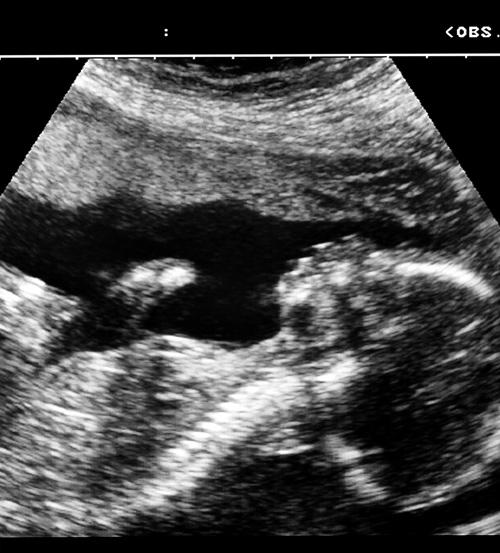

Fosterstørrelse bedømt med ultralydundersøkelse brukes til å fastsette svangerskapsalder, forventet termin og til å vurdere fosterets vekst. For at det skal gi mening å relatere vekst og utvikling hos det enkelte foster til en forventet norm, er det avgjørende at de biometriske referanseverdiene har høy kvalitet og er utarbeidet etter anbefalte kriterier for studiedesign og statistiske metoder. Det finnes i dag mange referanseverktøy – av varierende kvalitet.

Nå har britiske og amerikanske forskere undersøkt kvaliteten på disse biometriske studiene med henblikk på studiedesign, statistisk analyse og rapporteringsmetode (1). 83 studier fra 32 land publisert i perioden 1971 – 2008 tilfredsstilte inklusjonskriteriene.

– I Norge ble det for noen år siden utarbeidet og publisert nye biometritabeller for svangerskapet (2), sier seksjonsoverlege Synnøve Lian Johnsen ved Seksjon for fostermedisin og ultralyd, Kvinneklinikken, Haukeland universitetssykehus. – Tabellene var basert på en gravid populasjon i Bergens-området. Dataene ble innsamlet og analysert utelukkende i den hensikt å lage nye referanseverdier for svangerskapsalder og fostervekst. Det er betryggende for oss i Norge at av 83 bidrag som fylte kriteriene og ble inkludert i den systematiske oversiktsartikkelen, ble disse norske referanseverdiene vurdert å være blant de sju med høyest kvalitet, sier Lian Johnsen.